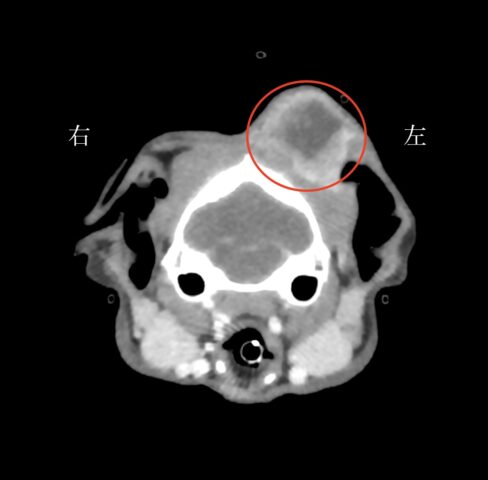

特にCT検査や細胞診検査、病理検査はより専門的な知識が必要です。

当院では、CT検査、細胞診検査、病理検査に特化した各診断医と連携を取り、検査所見を読み取ることで、より適切な診断を下させるよう努めています。

当院では約5秒で動物の全体をスキャンするCTがございます。これにより、動物への麻酔の負担を軽減して、撮影が行えます。また、動物の状態が悪い場合には麻酔をかけずに撮影を行うこともあります。撮影したデータは画像診断医“によって”正確な診断を行っております。動物のがんを早期に発見してあげることが何よりも動物に健康でいてもらえることに繋がりますので定期的な健診にも当院へお越しください。